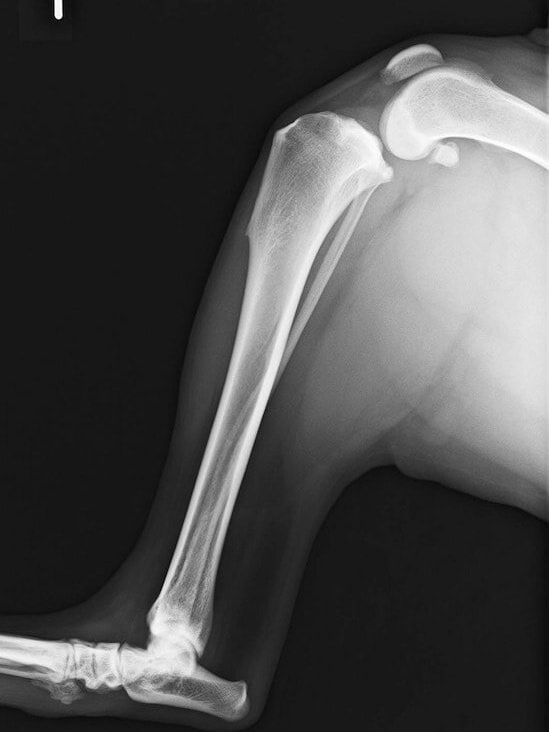

術前左後肢側面像

術前側面像

術前TPA計測

手術前